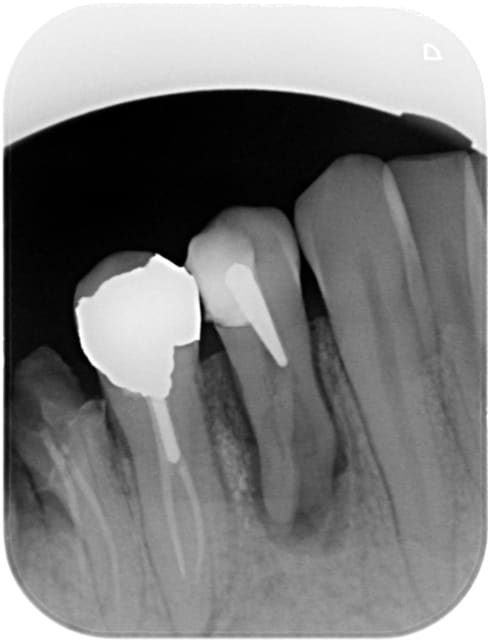

Trepo

26/04/2016 à 12h28

Bon désolé, je ne crois pas qu'il y ai un SC33 dans ce truc, à moins que ... Ceci dit j'aimerais autant pas, je pourrais reprendre l'endo à travers la Cr, même si Au moins 2 canaux ... (je suis bien con)

R2 p8tzop - Eugenol

Capture d  cran 2015 03 12 12.28 - Eugenol

chicot29

26/04/2016 à 19h28

Bon là il y en avait un. -)

Capture d e cran 2016 04 26 17.24 - Eugenol